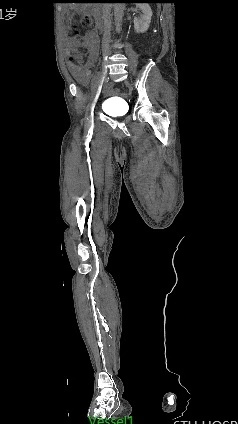

2.下肢深静脉血管CT成像(CTV)

随着人民饮食结构和生活习惯的改变,下肢深静脉血栓发病率每年递增,由其引发的肺栓塞,更是成为致命性的一种威胁。

CT静脉血管造影(CTV)检查能够直观、全面、准确、无创伤地观察病变血管管腔内外的情况,明确诊断血栓累及的范围和程度,为临床治疗提供可靠依据。